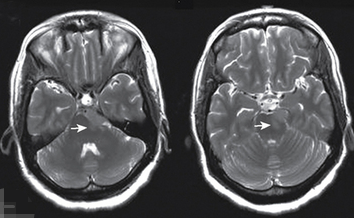

髓母细胞瘤手术的目标是在不损伤附近健康组织的情况下切除尽...

听神经瘤 的诊断通常是由患者的症状触发的。听神经瘤较常见的...